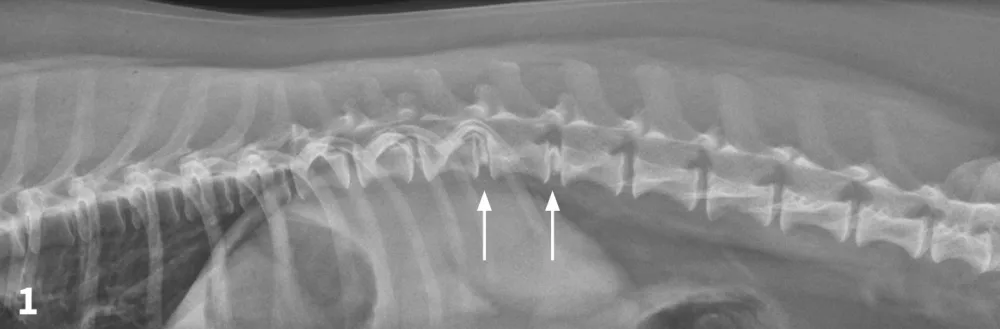

Figure 2

VD spinal radiograph. Mineralization and narrowing of the T13-L1 and L1-L2 disc spaces was noted (arrows).

The veterinarian administered 0.02 mg/kg acepromazine IM and 1 mg/kg morphine IM1 and obtained lateral and VD views of the TL vertebral column. (See Figures 1 & 2.) The radiographs showed no evidence of lytic change but did show mineralization and narrowing of the T13-L1 and L1-2 intervertebral disc spaces (arrows).